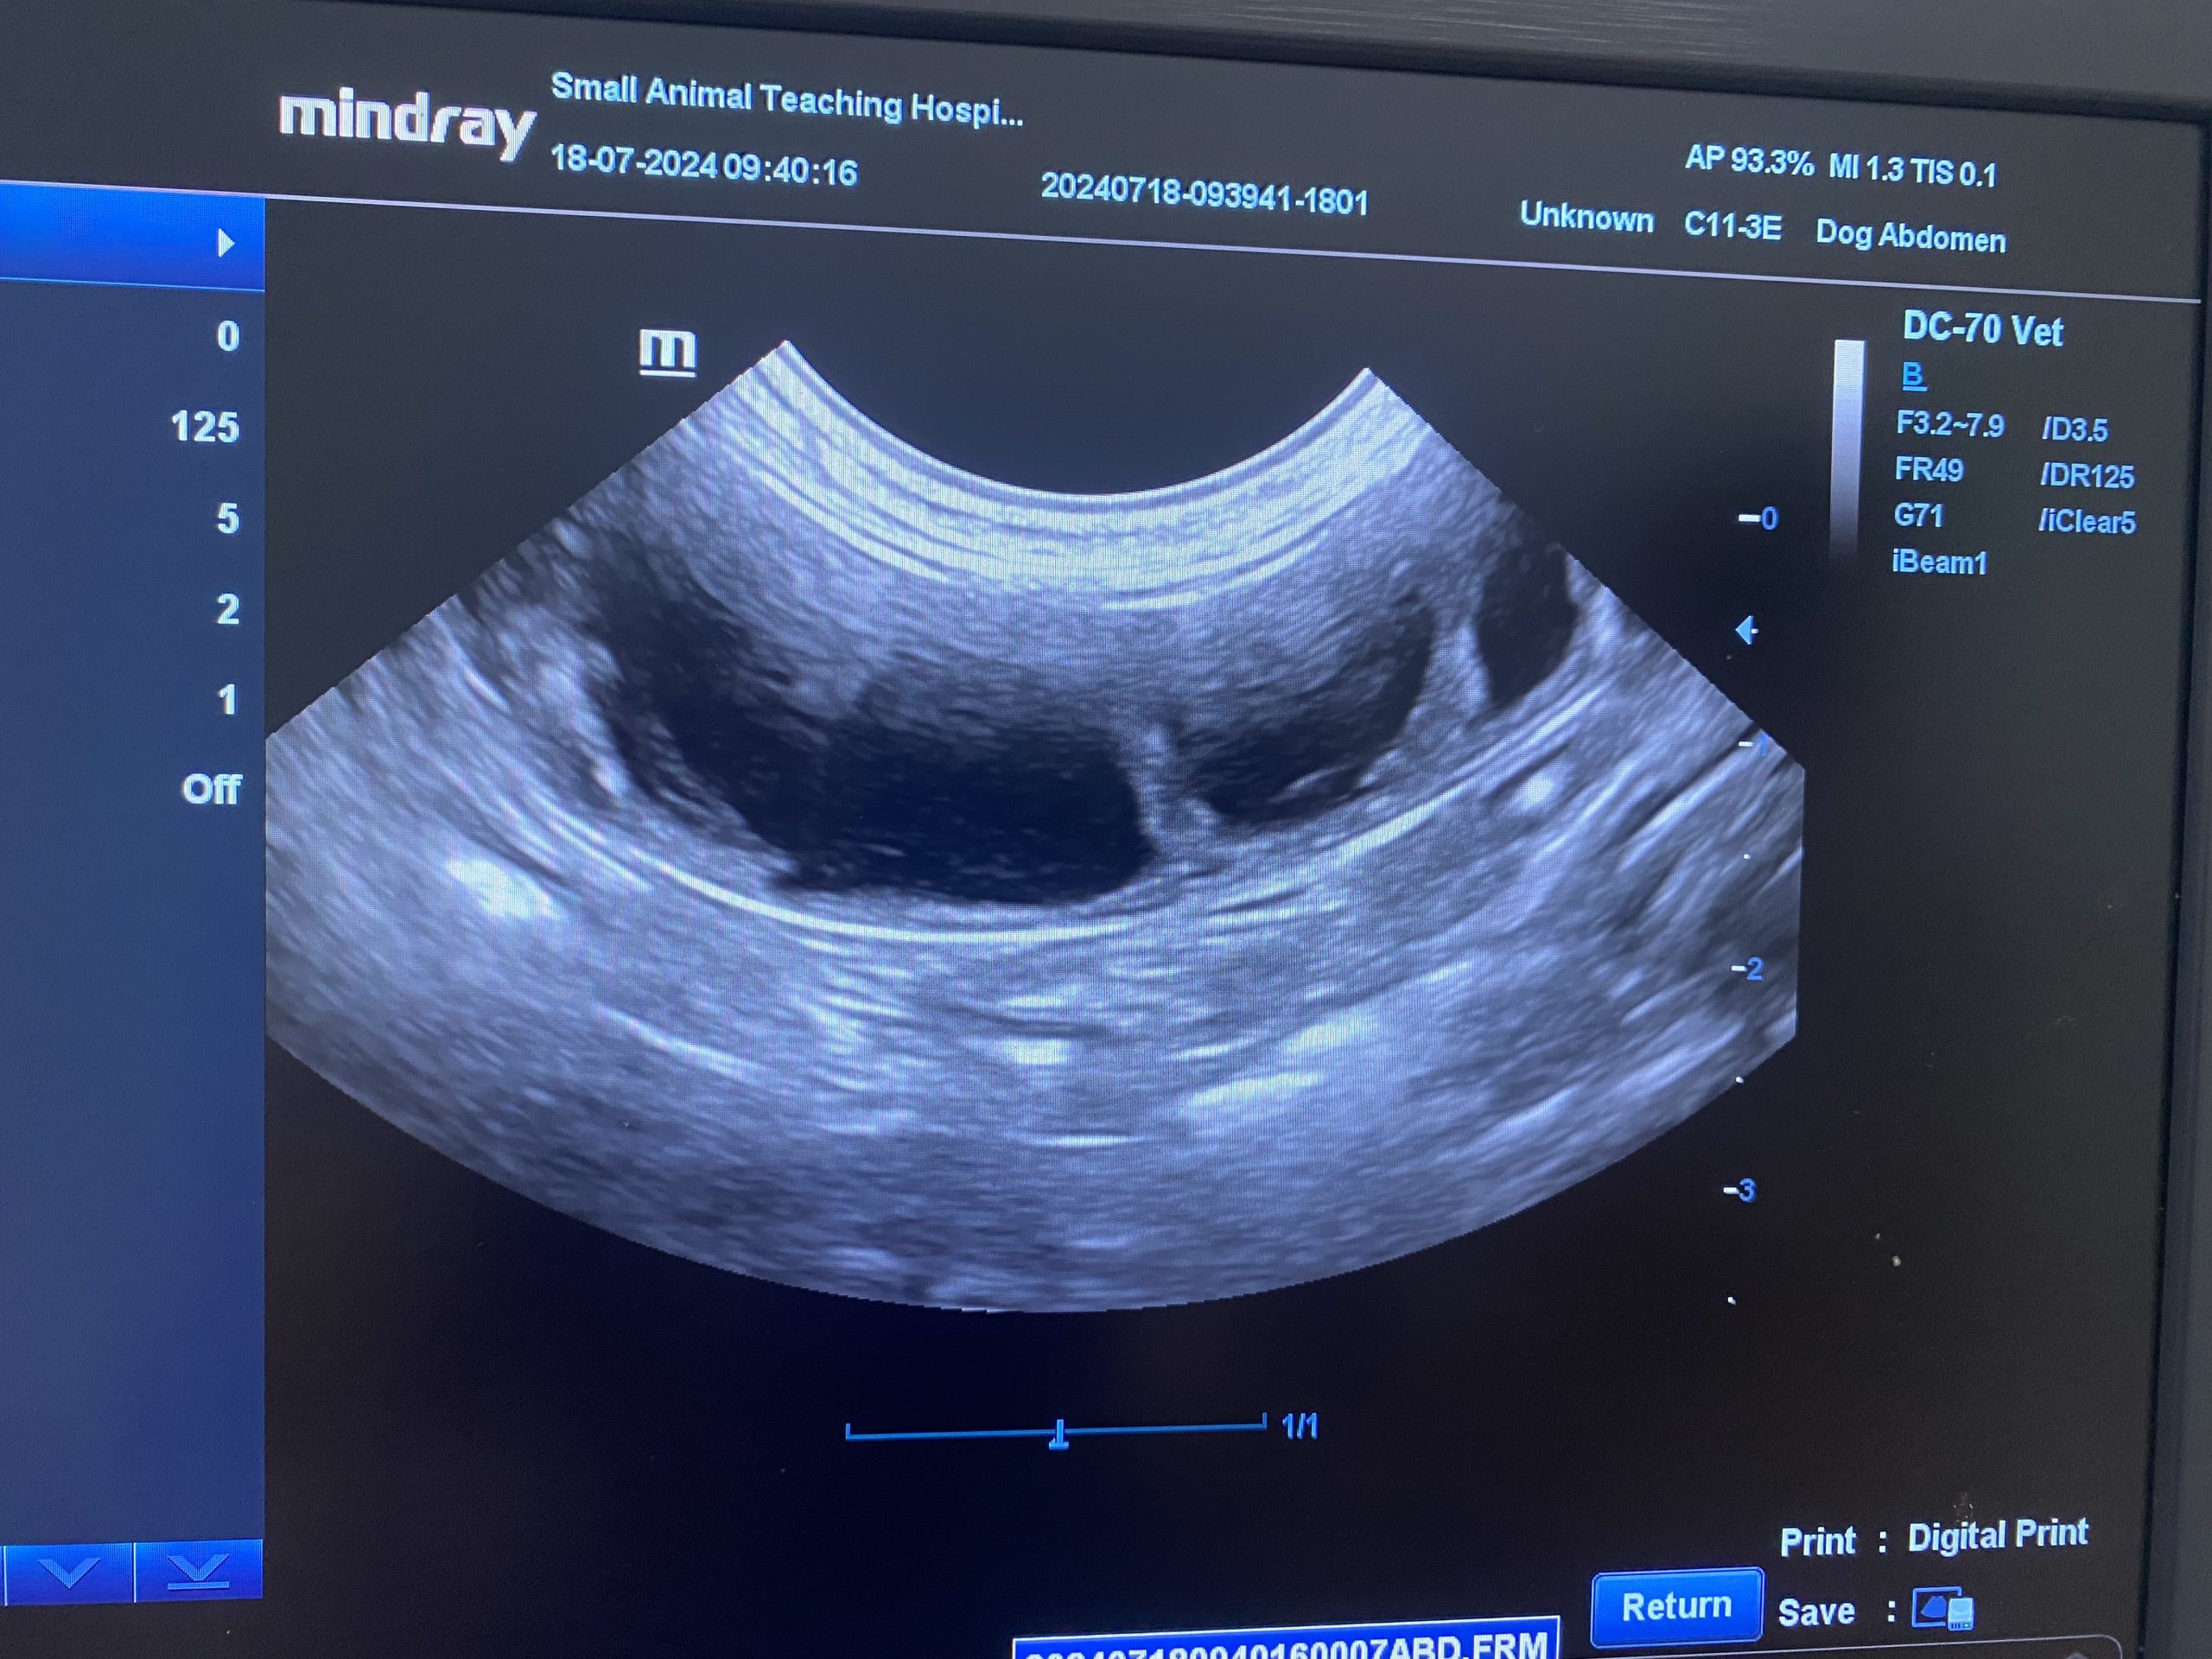

น้องสุนัขพันธุ์ชิวาว่าตัวเล็ก ถูกพาเข้ารับการรักษาที่โรงพยาบาลสัตว์ด้วยอาการ ซึม เบื่ออาหาร และมีของเหลวสีขาวขุ่นคล้ายหนองไหลออกจากอวัยวะเพศ (vaginal discharge) ทีมสัตวแพทย์ได้ทำการตรวจอัลตราซาวนด์ พบว่า มดลูกมีขนาดขยายผิดปกติจากการสะสมของของเหลว ซึ่งเป็นลักษณะของโรค มดลูกอักเสบ (Pyometra)